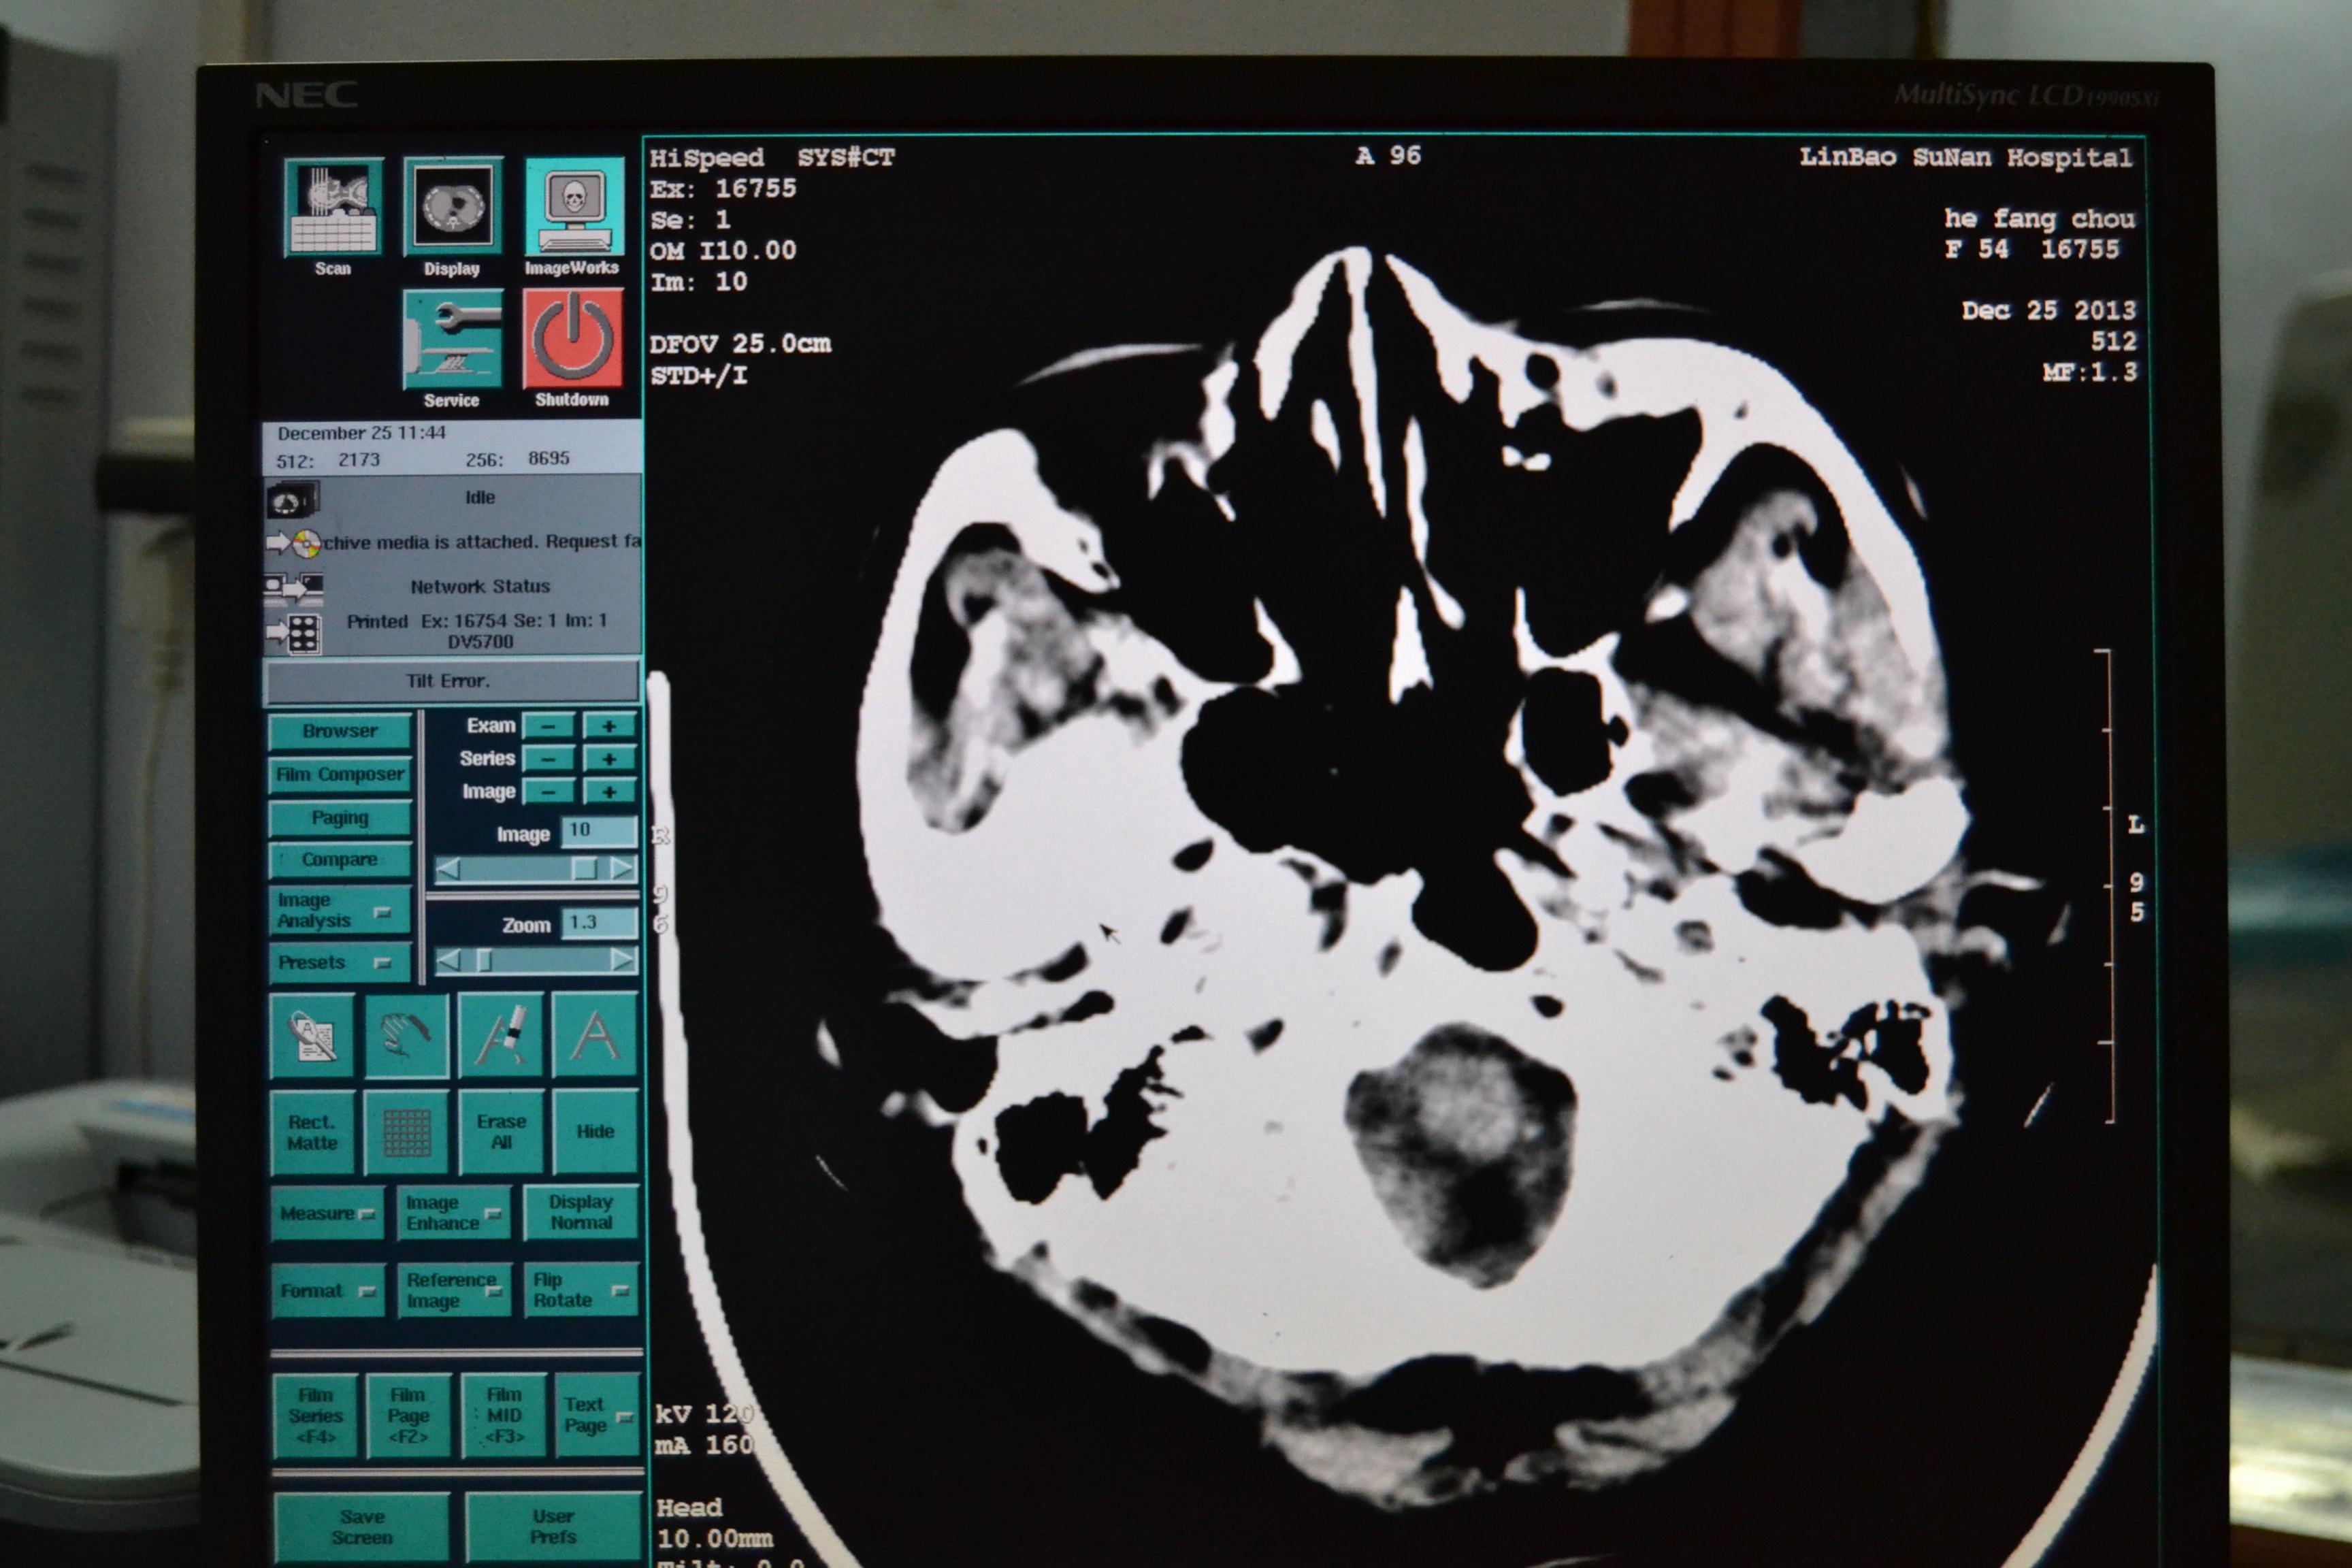

ct影像图显示,患儿鼻腔内有一圆形异物.

图片尺寸1200x1141